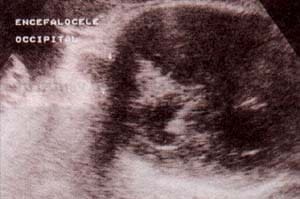

fig. 66. – (a). encefalocele occipital. 33 semanas. Corte longitudinal. se observa una masa de ecogenicidad mixta en la región occipital. |

fig. 66. – (b). corte transversal. es indispensable demostrar la solución de continuidad del defecto óseo para confirmar el diagnóstico. |